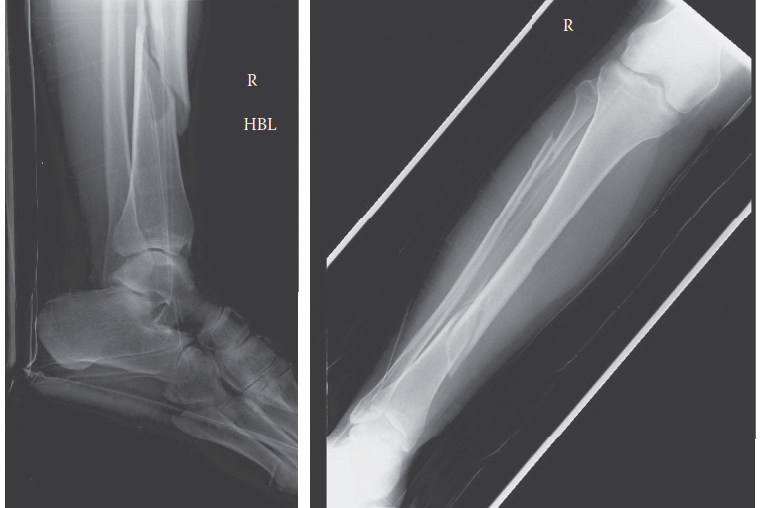

A 19-year-old male is brought in after an ATV accident when he was off-roading on his grandparent’s farm. He …

Can you describe the radiograph? This is an AP and lateral radiograph of the left ankle. It shows a bimalleol…